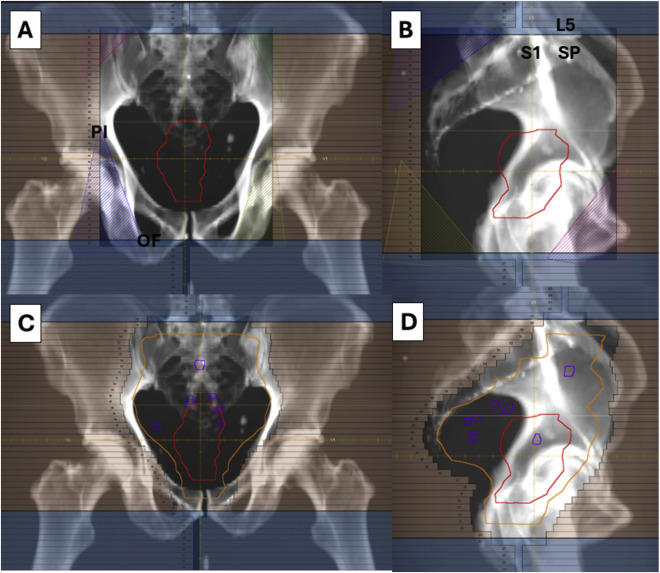

Từ những năm 1980, xạ trị đã trở thành một thành phần trong điều trị đa mô thức với ung thư trực tràng, tuy nhiên, cách thức xây dựng thể tích bia không ngừng được cải tiến và thay đổi theo thời gian. Trong lịch sử, các thể tích điều trị được vẽ trên phim cửa sổ trường chiếu (Portal film), theo các mốc xương (Hình 1), dựa trên kết hợp những hiểu biết về đường dẫn lưu bạch huyết của trực tràng và các dữ liệu ban đầu về vị trí tái phát thường gặp. Thông thường, một nhóm hạch vùng chậu được lựa chọnđ ể bao phủ trong thể tích bia lâm sàng nếu nguy cơ di căn hoặc tái phát xảy tại nhóm hạch này >=10%. Từ năm 2008, một số atlas và hướng dẫn xây dựng thể tích xạ trị đã được xuất bản nhằm cải thiện tính thống nhất trong thực hành xác định CTV, tuy nhiên, còn một số điểm vẫn còn chưa nhất quán (Bảng 1)

Đối với bệnh nhân này, với ung thư trực tràng trung bình giai đoạn cT3N1, thể tích bia dự phòng bao gồm các nhóm hạch: Mạc treo trực tràng, trước xương cùng, chậu trong và bịt (Hình 2). Nhóm hạch chậu ngoài được bổ sung đối với các bệnh nhân có bệnh giai đoạn cT4b và/hoặc có nhiều hạch mạc treo trực tràng và/hoặc hạch chậu trong. Nhóm hạch bẹn thường được đưa vào đối với các bệnh nhân có tổn thương lan xuống dưới đường lược hoặc tới 1/3 dưới của âm đạo. Chúng tôi thừa nhận rằng tỷ lệ tái phát tại nhóm hạch bẹn là thấp, chỉ khoảng 3,5% đến 4%, trong các loạt ca không bao phủ nhóm hạch bẹn dự phòng, tuy nhiên chúng tôi vẫn đưa nhóm hạch này vào do các kỹ thuật xạ trị hiện đại cho phép bao phủ mà không làm tăng độc tính đáng kể. Chúng tôi cũng thừa nhận rằng một số hướng dẫn (Bảng 1) khuyến cáo chỉ nên bao phủ khoang trước bên (Hạch bịt) ở những bệnh nhân có nguy cơ cao bị di căn vi thể; tuy nhiên, trong thực hành của chúng tôi, vùng này được bao phủ ở tất cả các trường hợp ung thư trực tràng tiến triển tại chỗ, do lợi ích kỳ vọng vượt trội so với nguy cơ khi mở rộng thể tích bia tại vùng này, phù hợp với các hướng dẫn đã được công bố khác.